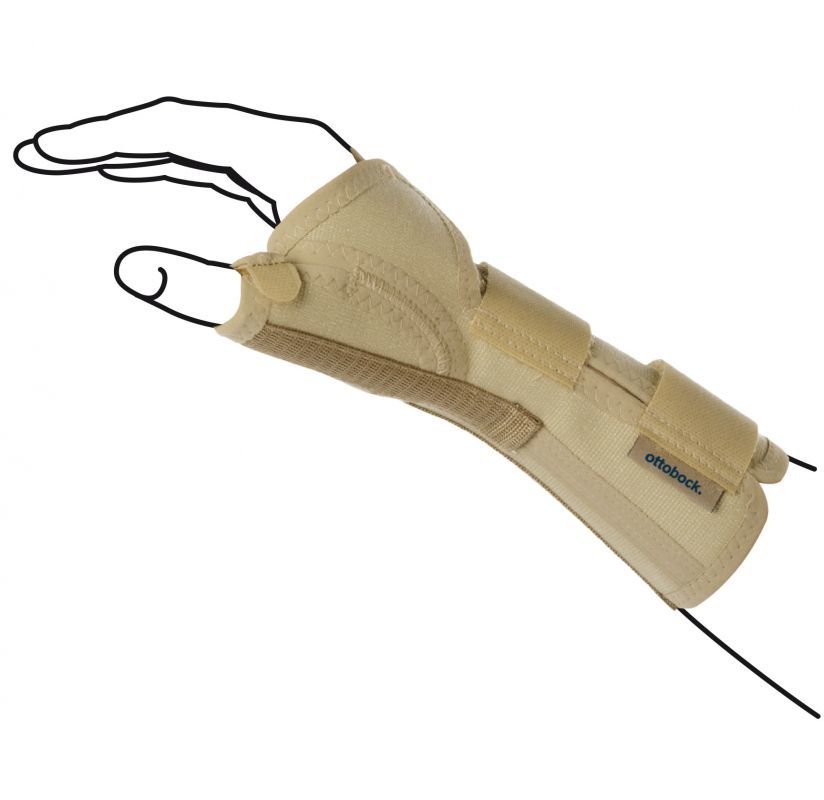

Otto Bock 4058 to orteza nadgarstka pozostawiający swobodny kciuk, wskazany do leczenia urazów nadgarstka i z powodzeniem stosowany w rehabilitacji nadgarstka. Orteza zapewnia mocną stabilizację i wzmocnienie nadgarstka. Orteza zabezpiecza przed niekontrolowanymi i niewskazanymi ruchami nadgarstka. Orteza wykonana jest z materiału przepuszczającego powietrze a anatomicznie wyprofilowane aluminiowe stalki od strony dłoni zapewniają skuteczną stabilizację.

Orteza z anatomicznie wyprofilowanymi szynami (na przód i tył dłoni lub bocznie od kości łokciowej), które zapewniają stabilizacje nadgarstka.

Orteza na rękę i przedramię z ujęciem kciuka. Stabilizuje nadgarstek i kciuk dzięki anatomicznie wyprofilowanym dwóm szynom, które można mocować od strony dłoniowej lub grzbietowej.

Manu Immobil unieruchamia Twoją dłoń i nadgarstek w tak zwanej pozycji funkcjonalnej — ułożeniu zapewniającym jak najbardziej efektywny przebieg leczenia urazów. Urządzenie całkowicie unieruchamia dłoń i zapobiega niekorzystnym z punktu widzenia rehabilitacji ruchom stawu. Niesie znaczną ulgę w bólu.

Orteza dłoni dla dzieci firmy Ottobock jest idealna dla Twojego dziecka, jeśli wymaga ono ortezy dłoni po urazie, operacji lub schorzeniu mającym wpływ na dłoń. Ortezy dłoni stabilizują wrażliwy obszar i zapewniają dziecku bezpieczeństwo podczas rutynowych czynności. Ograniczając ruch i obciążenie w ukierunkowany sposób, ortezy dłoni dla dzieci firmy Ottobock optymalnie wspierają proces gojenia dłoni dziecka.

Wspiera i stabilizuje nadgarstek i kciuk. Elastyczne mocowania na rzepy sprawiają, że ortezę bardzo łatwo się zakłada i zdejmuje. Wysoka jakość wykonania i wygodne dopasowanie.

Orteza na rękę i przedramię Manu 3D stosowana przy zmianach zwyrodnieniowych nadgarstka i leczeniu po urazach, deformacjach oraz przykurczach stawu. Orteza wykonana jest ze specjalnej, przewiewnej dzianiny, wpływając na wysoki komfort noszenia. Posiada proste zapięcie za pomocą pasków Velcro, oraz termoplastyczną szynę od strony dłoniowej. Wykonana z materiału, który nie pochłania wilgoci, co sprawia, że skóra pozostaje sucha

Działanie: zapewnia doskonałą stabilizację nadgarstka dzięki długiej, szerokiej szynie dłoniowej wykonanej z termoplastycznego tworzywa sztucznego.

Orteza na rękę i przedramię z ujęciem kciuka zapewniająca stabilizację nadgarstka dzięki termoplastycznej wewnętrznej szynie dłoniowej wykonanej z tworzywa sztucznego.

Plastyczna orteza na przedramię i dłoń z ujęciem kciuka AM-OSN-L-06 została skonstruowana w taki sposób, aby można było ją z łatwością stosować zarówno na prawą jak i lewą rękę. Dzięki temu stała się ona wyrobem bardziej uniwersalnym.

Długa otwarta orteza nadgarstka została wykonana według nowego bardziej anatomicznego kształtu, dzięki czemu lepiej stabilizuje palce, staw promieniowo-nadgarstkowy i nadgarstek.

Otwarta orteza przedramienia została wykonana według nowego bardziej anatomicznego kształtu, dzięki czemu lepiej stabilizuje staw promieniowo-nadgarstkowy i nadgarstek.

Orteza została w całości wykonana z nowego innowacyjnego surowca AirSanmed™ Wyrób posiada konstrukcję otwartą co ułatwia jego zakładanie na kończynę górną. Występuje on w wersji na prawą i lewą rękę. Zarówno w odcinku przedramienia, jak i dłoni łuskę można dowolnie kształtować nadając jej pożądany przez lekarza prowadzącego kształt. Dodatkowo przy pomocy załączonego do wyrobu kluczyka można regulować przywiedzenie i odwiedzenie dłoni.

Orteza ręki i przedramienia z ujęciem kciuka redukuje obrzęk i dolegliwości bólowe dzięki mikromasażowi i zwiększeniu ciepłoty. Wpływa korzystnie na ukrwienie uszkodzonych tkanek, pozwala uporać się ze stanem zapalnym. Dopasowana do kształtu ręki szyna dłoniowa oraz górne stalki zapewniają stabilizację stawu promieniowo-nadgarstkowego, przedramienia i nadgarstka. Dzięki szynie bocznej staw nadgarstkowo-śródręczny poddany jest mniejszemu obciążeniu. Produkt wyprodukowano z pianki oraz materiału bawełnianego. Poziom sztywności ortezy modyfikujemy dzięki wyjmowanym, aluminiowym stalkom. Rozmiar pozwala dopasować regulowane zapięcie.

Orteza ręki i przedramienia zwiększa ukrwienie uszkodzonych tkanek, redukuje obrzęk i pomaga usunąć stan zapalny. Dzięki mikromasażowi i ociepleniu pozwala uśmierzyć ból. Szyna dłoniowa, którą zaprojektowano z myślą o anatomicznych kształtach, oraz górne stalki świetnie stabilizują przedramię, nadgarstek, a także staw promieniowo-nadgarstkowy. Ortezę można swobodnie dopasować do wielkości ręki za pomocą regulowanego zapięcia. Wyprodukowana z pianki i bawełnianego materiału. Usztywnienie ortezy można zmniejszyć lub zwiększyć dzięki aluminiowym, wyjmowanym stalkom.

Elastyczny stabilizator nadgarstka i kciuka pozwala dzięki regulowanemu zapięciu, dostosować ortezę do anatomicznego kształtu kończyny. Konstrukcja opiera się na szynie dłoniowej i fiszbinach umiejscowionych na górnej części stabilizatora. Usztywnia nadgarstek i staw promieniowo-nadgarstkowy. Szyna boczna zapewnia stabilizację i możliwość odwiedzenie kciuka. Tkanina wykorzystana przy produkcji stabilizatora to elastyczny i kompresyjny materiał, swobodnie przepuszczający powietrze.

Elastyczny stabilizator nadgarstka przyspiesza wchłanianie się obrzęków i krwiaków oraz poprawia ukrwienie. Doskonale dostosowuje się do anatomicznego kształtu ręki dzięki zapięciu, które można modyfikować. Szyna dłoniowa, a także górne fiszbiny, stabilizują nadgarstek i staw promieniowo-nadgarstkowy. Kompresyjny stabilizator charakteryzuje się znaczą elastycznością. Świetnie przepuszcza powietrze.

Stabilizatory NEOX oprócz właściwości stabilizowania i odciążania, poprzez zastosowanie termoaktywnego neoprenu z systemem HTCAS™ by NEOX wytwarzają korzystny dla skóry mikroklimat. Dzięki możliwości kontroli termicznej, głęboko rozgrzewają mięśnie i stawy bez przegrzewania i podrażniana skóry.

Wykonany z termoaktywnego materiału AIR-FLEX™ zapewniającego naturalny proces cyrkulacji powietrza.

Posiada 3 szyny zapewniające najwyższy stopień stabilizacji i odciążenia nadgarstka.

Wykonany z termoaktywnego materiału AIR-FLEX™ zapewniającego naturalny proces cyrkulacji powietrza. Posiada 3 szyny zapewniające najwyższy stopień stabilizacji,

SP-878 / SP-879 Orteza nadgarstka – długa prawa/lewa. Wykonana z innowacyjnego materiału w opatentowanej technologii MultiCeramic. Materiał antybakteryjny, hipoalergiczny, ze wzmocnioną siłą wchłaniania i odprowadzania wilgoci.

Lekka, estetyczna i niepowodująca podrażnienia skóry: orteza kciuka Rhizo Forsa stabilizuje staw siodełkowy i bazowy kciuka nie ograniczając codziennej aktywności. Cechy produktu: stabilizacja pierwszego stawu śródręczno-paliczkowego oraz stawu siodełkowego kciuka; łatwość użytkowania; niewielka waga; estetyczny design; nie powoduje podrażnień; orteza wykonana z delikatnego, przyjemnego w dotyku materiału; atrakcyjne wzornictwo i kolorystyka. Zastosowanie: urazy wiązadła pobocznego oraz stawu śródręczno-paliczkowego (np. tzw. „kciuk narciarza”); inne obrażenia obszaru nadgarstka i kciuka; podrażnienie i zmiany zwyrodnieniowe stawu śródręczno-paliczkowego oraz/lub stawu siodełkowego kciuka (np. rhisartroza).

Orteza nadgarstka, stabilizator Manu Sensa pozwoli Ci poruszać się pewnie i bezpiecznie, bez ograniczeń. Delikatnie wspomaga proces gojenia i pomaga zmniejszyć ból. W przypadku urazów stawu nadgarstkowego, wspomaganie procesu gojenia dzięki wsparciu nadgarstka jest bardzo rozsądne.

Włókna antybakteryjne znajdujące się w dzianinie skutecznie hamują rozwój bakterii i hamują powstawanie przykrego zapachu. Szyna nadgarstka jest anatomicznie wyprofilowana i może być indywidualnie dopasowana ograniczając zakres ruchu w stawie nadgarstka.

Szynowa orteza ręki AM-SP-01 to doskonała orteza na urazy dłoni typu bokserskiego oraz skuteczne zaopatrzenie ortopedyczne w przypadku złamań lub zwichnięć poszczególnych palców ręki. Orteza unieruchamia wybrane palce, pozwala na ich dowolne ustawienie, kontroluje ich ruchy i umożliwia ustawienie właściwego poziomu ich stabilizacji. Grzbietowe ustawienie szyny oraz ażurowa konstrukcja ortezy umożliwia stosowanie jej również bezpośrednio po zabiegu operacyjnym. Jest to najbardziej uniwersalna orteza dłoni do stosowania przy wszelkich urazach rąk, złamaniach śródręcza, uszkodzeniach więzadła pobocznego i urazach paliczków.

Wyrób posiada konstrukcję otwartą, co ułatwia jego zakładanie na kończynę oraz regulowane zapięcie, co czyni ortezę jeszcze bardziej uniwersalną i ułatwia dopasowanie do każdego kształtu dłoni. W ortezie zamontowano taśmę stabilizującą kciuk, której nadmiar po dopasowaniu należy odciąć.

Ażurowa orteza nadgarstka została wykonana według nowego bardziej anatomicznego kształtu, dzięki czemu lepiej stabilizuje staw promieniowo-nadgarstkowy i nadgarstek.

Orteza wielopalcowa Digimax O-1770 Reha Fund umożliwia stabilizację od jednego do czterech palców ręki (poza kciukiem). Wykonana z neoprenu i weluru zapewnia swobodny przepływ powietrza i pomaga utrzymać odpowiednią ciepłotę ciała. Stabilizator idealnie dopasowuje się do kształtu ręki, a boczne zapięcie na rzep ułatwia zakładanie/ściąganie. Orteza unieruchamia staw, ale nie ogranicza swobody ruchów.

Orteza palcowa ręki Digimax Plus O-1771 Reha Fund OMax to produkt medyczny wykorzystywany do rehabilitacji kontuzjowanej dłoni. Orteza unieruchamia jeden z czterech palców dłoni (poza kciukiem) i odciąża staw śródręczno-paliczkowy. Produkt ortopedyczny pasuje zarówno na prawą, jak i lewą dłoń oraz jest dostępny w rozmiarze S i M.

SPECIAL PROTECTORS SP-208 Wykonana z innowacyjnego neoprenu w opatentowanej technologii CoolMax AIRPRENE.

SPECIAL PROTECTORS SP-872/SP-873 Orteza nadgarstka – krótka prawa/lew. Wykonana z innowacyjnego materiału w opatentowanej technologii MultiCeramic. Materiał antybakteryjny, hipoalergiczny, ze wzmocnioną siłą wchłaniania i odprowadzania wilgoci.